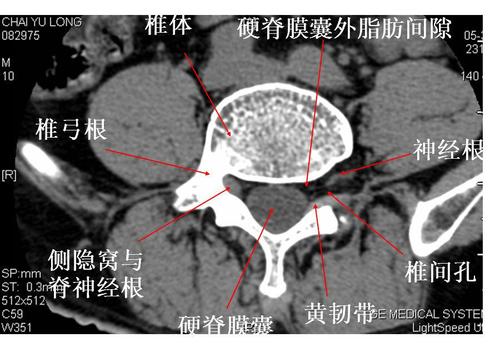

腰椎椎体侧隐窝解剖及狭窄常见原因

腰椎侧隐窝ct解剖图